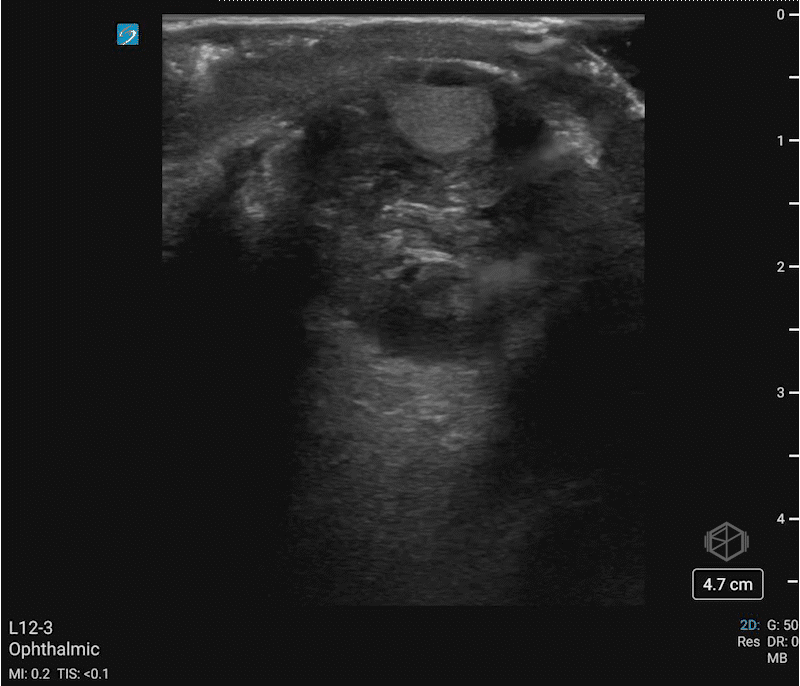

Dr. Simon very carefully performed an ocular ultrasound:

Upon seeing this he immediately terminated the ultrasound having made the diagnosis. With multiple differentials to consider this ultrasound has some great findings. The anterior chamber of the eye demonstrates layering fluid. The vitreous body is completely heterogenous instead of anechoic. There is no guitar pick sign or anechoic material posterior the eye that would indicate a retrobulbar hematoma. The patient was evaluated by ophthalmology that confirmed his diagnosis and the patient was transferred for ophthalmologic surgery.

Diagnosis: Traumatic globe rupture with significant vitreous hemorrhage and a hyphema

• A hyphema appears as a settled echogenic blood within the aqueous of the anterior chamber.

• This patient has a significant vitreous hemorrhage/intraocular hematoma as noted by the entire vitreous body filled with echogenic material.

• The globe rupture is suggested by the decreased size of the globe, indicating loss of pressure or vitreous.